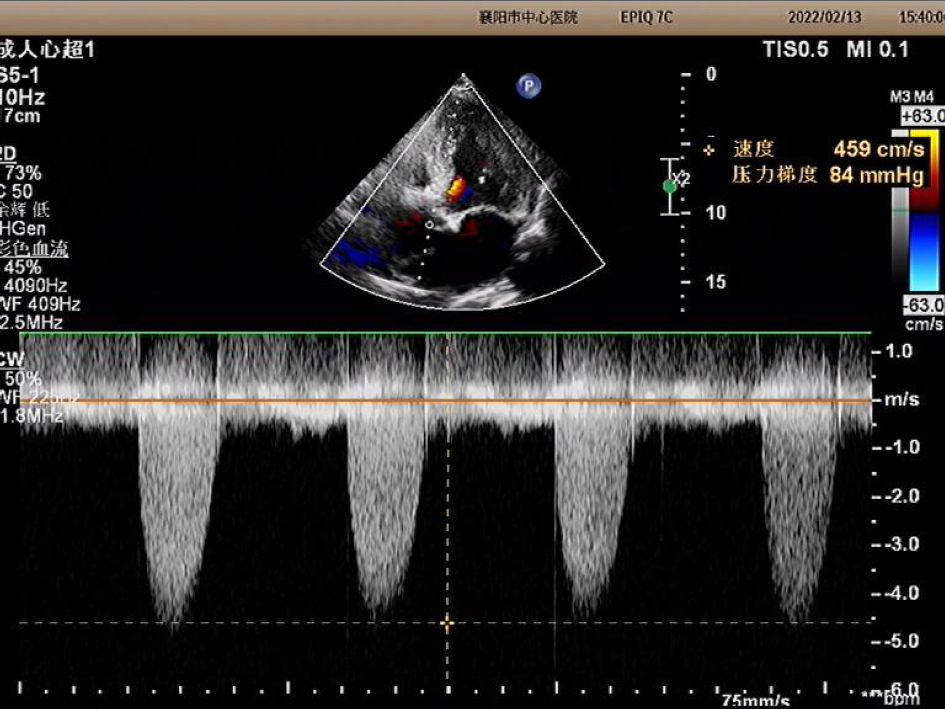

2022年2月13日超声图像

主动脉瓣峰值流速:4.59M/s;

升主动脉内径:55mm;

平均跨瓣压差:84mmHg;

左室射血分数EF值:46%;

主动脉瓣增厚,回声增强,瓣叶形态显示不清,瓣膜开放明显受限;

升主动脉瘤形成;心包积液;

主动脉瓣口左室流出道侧见舒张期轻度反流信号。

诊断:主动脉瓣重度狭窄。经团队讨论和患者家属商议后决定,行TAVR手术治疗。